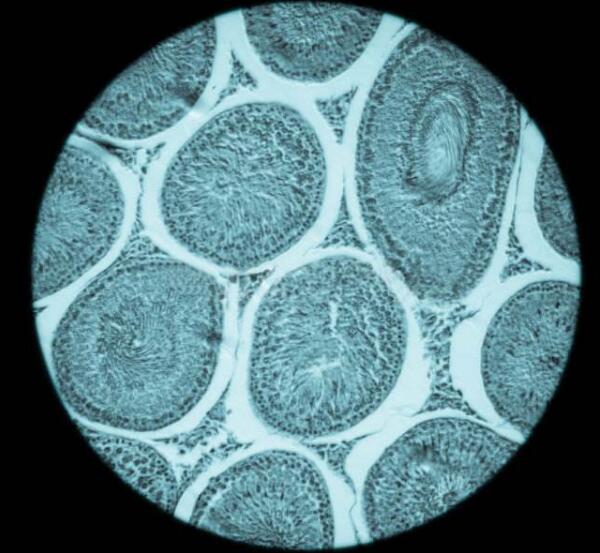

美国梦美HRC生殖专家介绍到,女性出生时卵巢内约有200万个卵泡,儿童时期大多数的卵泡会退化,到了青春期仅剩30万个左右。正常情况下,每个月经周期会有几个到几十个卵泡进入发育轨道,在体内激素的控制下,经过募集、选择的过程,通常只有一个卵泡会发育成熟并排出,一生排出的成熟卵子大约为400个左右,其余基础卵泡则自行闭锁、消亡。

而促排卵则是通过7~9天的持续用药,为基础卵泡的发育提供充足养料,将那些本应进入闭锁期的基础卵泡重新拉回生长队列中,促使多颗基础卵泡同时发育成熟,以获取多个卵子。而促排卵并非提前动用卵巢储备,所以不存在试管促排卵会导致卵巢早衰的情况。